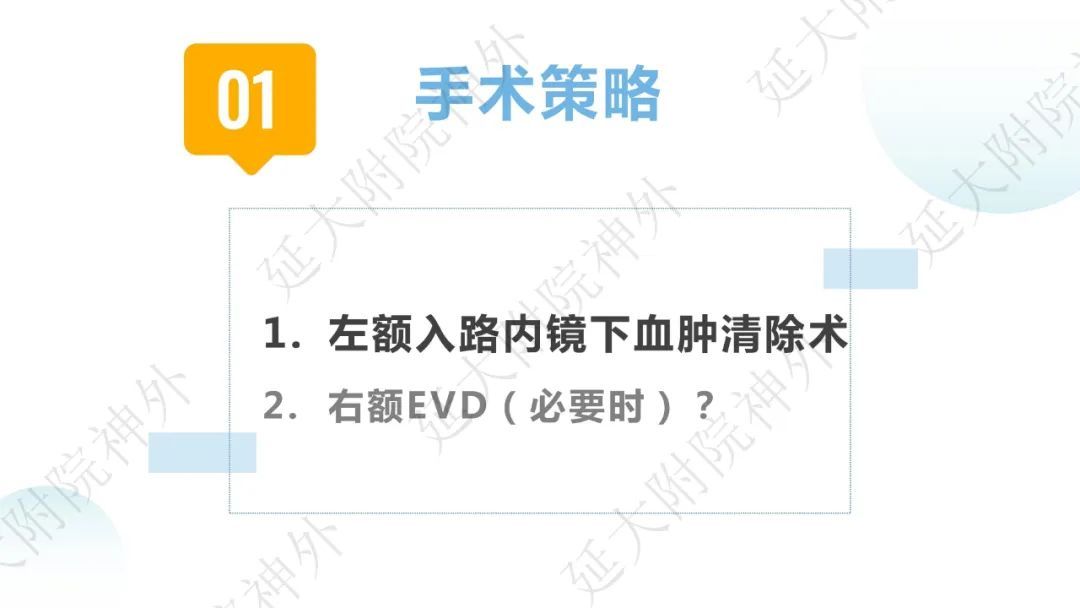

今天为大家分享的是《监测有道丨颅脑创伤-神经重症周刊》第332期,由延安大学附属医院神经外科贾云峰主任医师带来的:左侧基底节区出血破入脑室一例神经内镜下血肿清除术,欢迎阅读、分享。